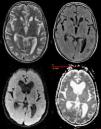

Mujer de 68 años que ingresa con cuadro progresivo de cefalea holocraneal, deterioro cognitivo de rápida evolución y síndrome constitucional. Una tomografía computarizada torácica (fig. 1) evidenció una masa en zona parahiliar del pulmón derecho. Como parte del estudio se realiza una RM cerebral que mostró niveles rectos de interfase líquido-sólido en las astas occipitales (fig. 2), con restricción del movimiento del agua libre en secuencia ADC y moderadamente brillante en secuencias de difusión altamente indicativo de corresponder a depósitos celulares.